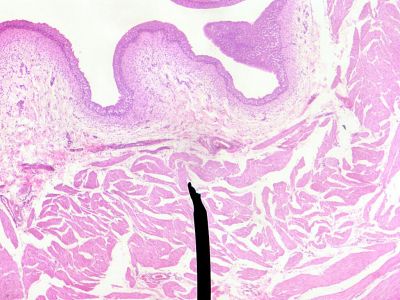

Bladder - histology slide

This is a histology slide of the bladder.

Image by Jpogi via Wikipedia. Public domain.

No changes were made to the original image downloaded (note: this version was downloaded at reduced resolution from Wikipedia).